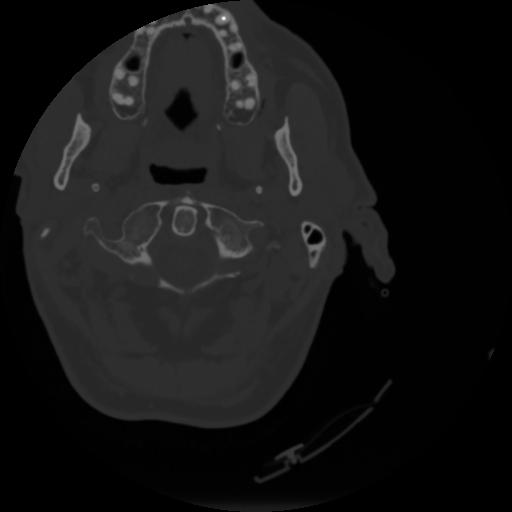

4 CEREBRO,,Vol,0.5,CEREBRO,,